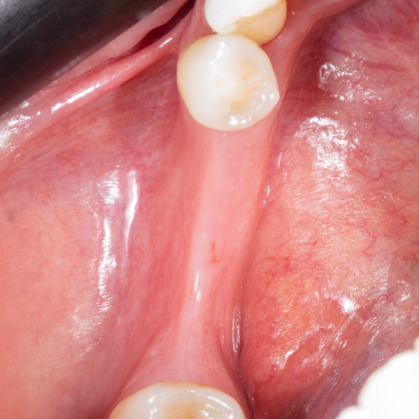

Ana sayfa > Klinik Vakalar > Diş çekiminin yıllar önce yapılmış olmasına bağlı olarak ince kemik varlığında implant ve kemik grefti uygulandı

Diş çekiminin yıllar önce yapılmış olmasına bağlı olarak ince kemik varlığında implant ve kemik grefti uygulandı